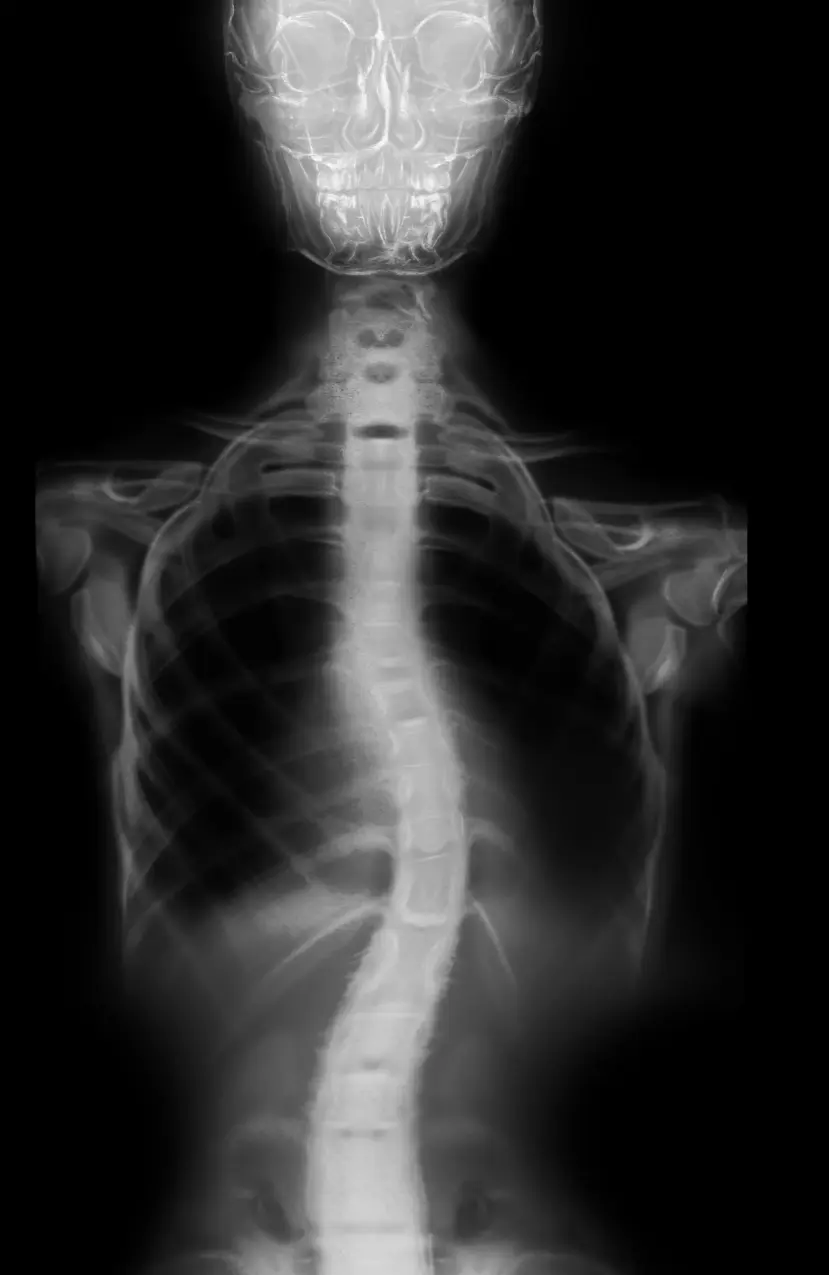

Antes

Después